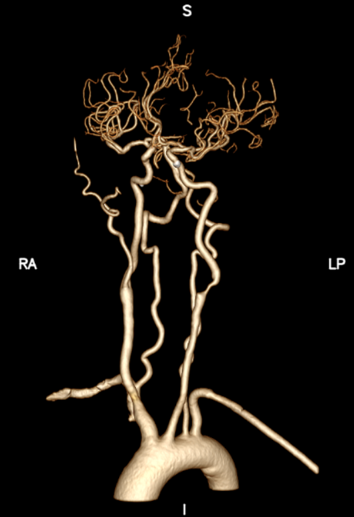

头颈部CTA

波科支架怎么样径技-弓上病例大赏|第205期·放疗后症状性颈动脉狭窄支架置入治疗一例_https://www.jmylbn.com_新闻资讯_第9张

波科支架怎么样径技-弓上病例大赏|第205期·放疗后症状性颈动脉狭窄支架置入治疗一例_https://www.jmylbn.com_新闻资讯_第10张

波科支架怎么样径技-弓上病例大赏|第205期·放疗后症状性颈动脉狭窄支架置入治疗一例_https://www.jmylbn.com_新闻资讯_第11张